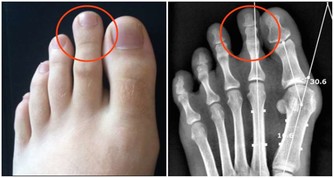

靜脈曲張。女性更容易出現這種情況,20歲後就有可能發生。一旦腿上的血管突然非常清晰,彎彎曲曲像蛇一樣,說明腿部血管出現了勞損。

髖膝關節疼痛。幾乎所有關節都會隨著年紀增大而變得脆弱,特別是髖、膝這兩處關節。如果你發現在下樓梯、蹲下或跳躍時出現不適,甚至腿部有摩擦磨損、卡住動不了的感覺,說明關節已經急需保護了。